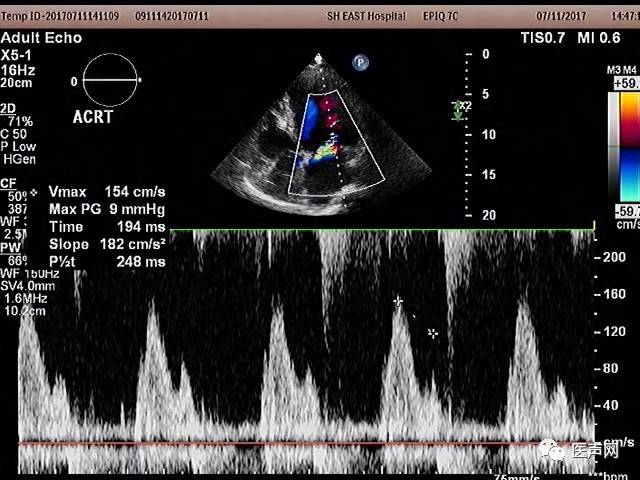

术后彩超优化

术后程控:

术后一天

程控模式:

DDD

程控参数:

Adaptive Bi-V and LV

PAV/SAV:自动

VV:自动

术后彩超: